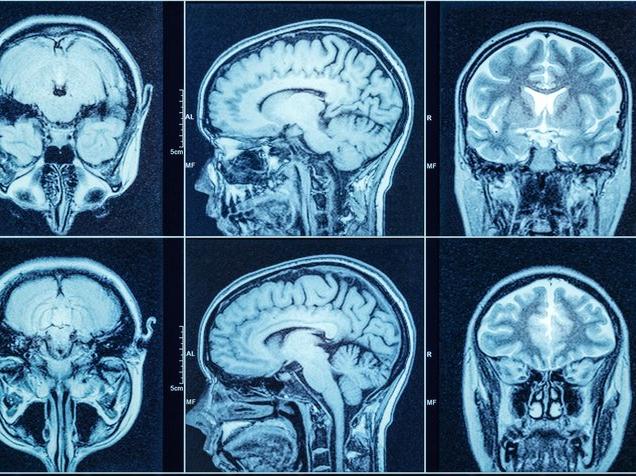

Araştırma, beynin bilinçsiz olarak belirli deneyimleri olumlu veya olumsuz bir duygu veya değer ile nasıl ilişkilendirdiğine odaklandı. Örneğin; olumsuz bir duyguyu, çiğnediğinizde korkunç derecede acı olan bir bitkiyle ilişkilendirirseniz, onu tekrar yemeyi denemeniz pek olası değildir. Beynin de bu duyguları bir bellekle ilişkilendirme yeteneğine değerlik ataması denir.

2016 yılında, Tye liderliğindeki bir ekip, beynin bazolateral amigdala (BLA) olarak bilinen bir bölgesindeki bir grup hücrenin, değerlik atamasına yardımcı olduğunu keşfetti. Bir deneyime pozitif bir değerlik eklendiğinde bir dizi BLA hücresi aktive edildi.

Hayvanlar üzerindeki araştırmada negatif bir değerlik devreye girdiğinde ayrı bir BLA hücresinin aktive olduğu görüldü.